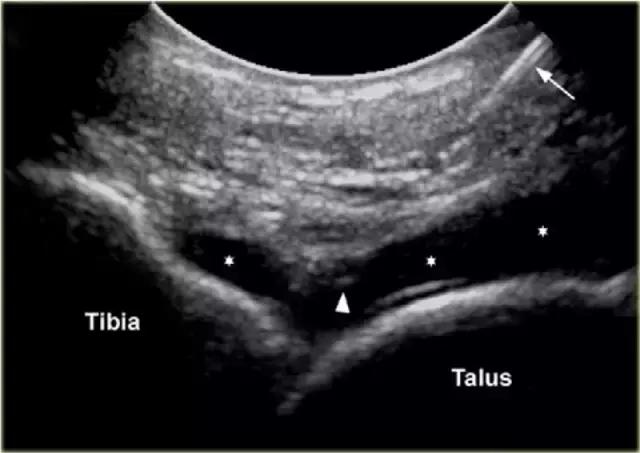

胫骨关节 CT或MR关节镜可用于查询韧带,骨软骨或软骨损伤,评价自由体或查询骨软骨病变的稳定性。对于踝关节(胫骨关节)的注射,患者仰卧,足部轻微的跖屈。用超声波检查胫骨关节的内侧,以确定合适的注射部位,同时检查任何过量的关节液。我们使用小型弯曲阵列8 MHz传感器,但如果优选,可以使用18-12 MHz线性阵列传感器。 探头的长轴保持在矢状面内。

通常为22号(长度:30mm)的针被引入与在前关节空间的内侧上的换能器的长成像轴线,内侧到前胫骨韧带,避免韧带和血管。应该确定距骨穹顶和悬垂的前胫骨唇。 针头在胫骨远端成角度地进入远侧胫骨的腹侧唇下的关节,瞄准远侧胫骨的关节表面。感觉到接触,并且再次确保针尖离开胫骨软骨并且斜面面向接头。

将8-10ml的对比剂注入胫骨关节,并且看到前囊与流体一起膨胀。

患者不应该有疼痛而抵抗。